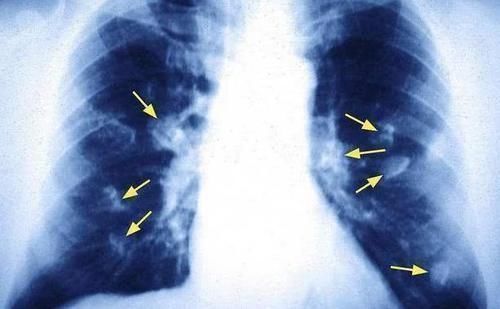

在我们的认知中,癌症的治愈性并不是很高,不过这也相对于中晚期患者而言;如果你能够在癌症早期就能够发现蛛丝马迹,从而采取相对应的措施和积极治疗,那么癌症病情还是能够得到很好的控制,甚至有些人已经逆转了癌症。目前来说,很多朋友并没有定期进行体检工作的习惯,这也是很容易遗漏早期发现癌症的一个环节。说到癌症中的肺癌,大家对它也不是很陌生,肺癌在早期也是有蛛丝马迹的,当你的身体出现这4个表现,可能是肺癌在路上的信号,别不当回事!

■肺癌到来之前,身体也是有蛛丝马迹的,注意这4个身体表现!